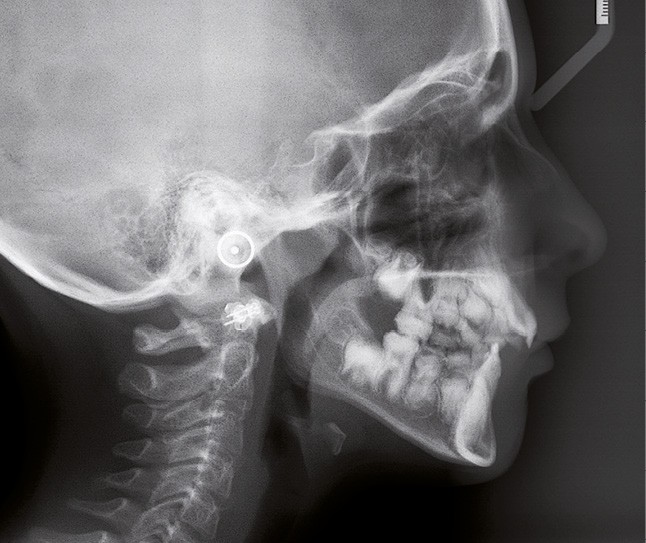

Il existe des anomalies dentaires (tabl. I) [1-12], mais aussi occlusales associées aux AI (fig. 1 et 2).

Selon de nombreuses études, l’anomalie occlusale la plus fréquemment retrouvée en association avec les AI est l’infraclusion antérieure, puisqu’elle est retrouvée chez 22 à 64 % des patients présentant cette affection, et encore plus chez les femmes [2,8,13-19]. Cette anomalie touche tous les types d’AI mais à des degrés très divers. Son incidence semble élevée dans les formes hypominéralisées, moindre dans les formes hypoplasiques et nettement moindre dans les formes hypomatures [8,17,18]. La sévérité de l’atteinte amélaire ne semble pas corrélée avec la présence ou l’intensité de cette malocclusion [17].

En 1982, Rowley et al. [18] ont montré que 44 % des patients atteints d’AI dans leur échantillon, présentaient un angle plan maxillaire (épine nasale antérieure – épine nasale postérieure) /plan mandibulaire (point gonion – point menton) supérieur à 34°, alors que la norme…